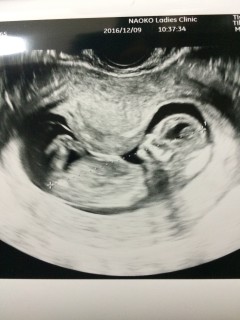

初めての腹部エコーでした。 形もしっかりしていて、 鼻が高いねってパパと話をしました。 エコーのはじめは寝ていた様ですが 途中から起きてよく動いてて とってもかわいかったです。 性別は次の検診かな?!! 初めてなので不安も多いですが 赤ちゃんの成長が楽しみです。